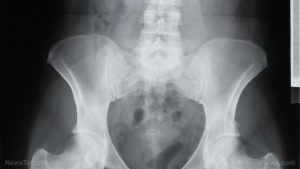

Bone cancer is a cancerous tumor of the bone that damages normal bone tissue. However, cancer that starts in a bone is rare. On the other hand, cancer that has spread to the bone from a different part of the body is more common. Bone cancer has three types — osteosarcoma, chondrosarcoma, and Ewing’s sarcoma. Osteosarcoma develops most frequently in individuals who are 10 to 19 years old. It is more common in the knee and upper arm. Chondrosarcoma is a type of bone cancer that starts in the cartilage, and develops in people over 40 years old. Meanwhile, Ewing’s sarcoma develops most frequently in children and teens below 19 years old, and is more common in boys than girls.

The main body system that is harmed by bone cancer is the skeletal system.